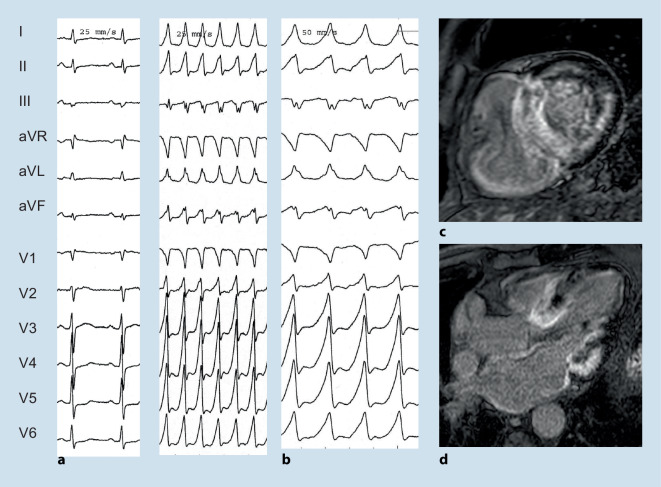

Fig. 4.

A 51-year-old male with genetically proven Anderson–Fabry disease and a history of aborted sudden cardiac death 4 years before presentation. After initial diagnosis of an assumed viral myocarditis, the patient presented 4 years later to the authors’ department with recurrent ventricular tachycardia (VT) (b). Late-stage Fabry disease with cardiac, neurological, and renal impairment was diagnosed. Cardiac magnetic resonance imaging (d,f) demonstrated apical and extensive posterolateral scarring that correlated to electroanatomical bipolar CARTO maps (c,e). The patient underwent endo- and epicardial VT ablation

Fig. 5.

Electrocardiogram (a) of a 74-year-old male with wild-type ATTR amyloidosis initially presenting with a sustained ventricular tachycardia (b). Note the prominent diffuse late gadolinium enhancement on cardiac magnetic resonance imaging (c,d)